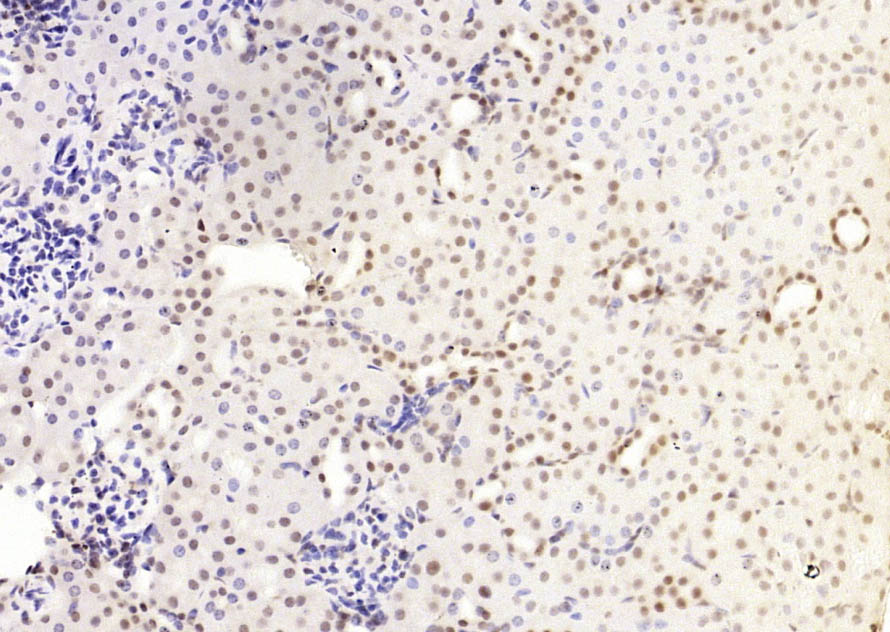

Paraformaldehyde-fixed, paraffin embedded (mouse testis); Antigen retrieval by boiling in sodium citrate buffer (pH6.0) for 15min; Block endogenous peroxidase by 3% hydrogen peroxide for 20 minutes; Blocking buffer (normal goat serum) at 37°C for 30min; Antibody incubation with (HP1 gamma) Monoclonal Antibody, Unconjugated (bsm-33375M) at 1:200 overnight at 4°C, followed by operating according to SP Kit(Mouse) (sp-0024) instructionsand DAB staining.

Paraformaldehyde-fixed, paraffin embedded (mouse kidney); Antigen retrieval by boiling in sodium citrate buffer (pH6.0) for 15min; Block endogenous peroxidase by 3% hydrogen peroxide for 20 minutes; Blocking buffer (normal goat serum) at 37°C for 30min; Antibody incubation with (HP1 gamma) Monoclonal Antibody, Unconjugated (bsm-33375M) at 1:200 overnight at 4°C, followed by operating according to SP Kit(Mouse) (sp-0024) instructionsand DAB staining.

Paraformaldehyde-fixed, paraffin embedded (mouse liver); Antigen retrieval by boiling in sodium citrate buffer (pH6.0) for 15min; Block endogenous peroxidase by 3% hydrogen peroxide for 20 minutes; Blocking buffer (normal goat serum) at 37°C for 30min; Antibody incubation with (HP1 gamma) Monoclonal Antibody, Unconjugated (bsm-33375M) at 1:200 overnight at 4°C, followed by operating according to SP Kit(Mouse) (sp-0024) instructionsand DAB staining.